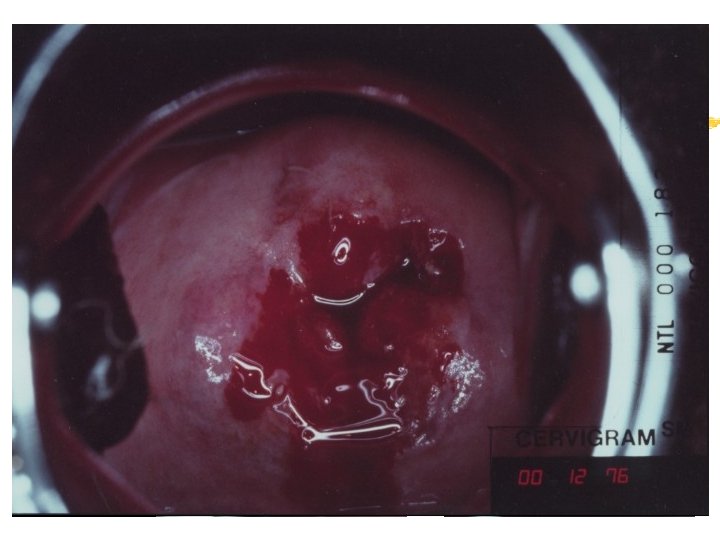

The Alternative…Downstaging !!! The detection of the disease at an earlier stage when still curable… Just Insert a speculum and look at the cervix

Warning signs of early cervical cancer 1. Yellowish and friable epithelium 2. Abnormal contour 3. Ulceration 4. Atypical vessels 5. Very severe colposcopic atypia 6. Large, significant lesion 7. Canal lesion, going out of range 8. Perimenopausal and post radiation

Mimics of cervical cancer 1. Severe cervicitis e. g. , herpes, syphilis 2. Benign ulceration e. g. , trauma 3. Foreign body reaction 4. Granulomatous cervical conditions 5. Granuloma inguinale 6. Lymphogranuloma venereum 7. Schistosomiasis 8. Cervical condylomata Cololposcopy aids differentiation. Histology is the gold standard

Cervicography: This is NOT Colposcopy High-quality colposcopic-type photography of the cervix Cervicoscope - Hand-held camera with a macrolens and a ring-flash Cervicogram - 35 -mm photo slide is taken Principles Recognition of lesions by means suitable magnification and illumination Fix up the problems of colposcopy 1. a less expensive form 2. noninvasive method 3. do not require expert skill

Procedures of cervicography A) Taking a 35 -mm cervicogram (1) Insert speculum and open as wide as possible … expose an entire cervix and upper vagina (2) Apply first application of 5% acetic acid by dabbing … cleanse the cervix of blood and mucus (3) View the cervix through the cervicoscope … allows time to begin taking epithelial change (4) Apply second application of acetic acid. (5) Take two cervicogram pictures B) Developing the images C) Interpreting a magnified image that was projected on the screen (1) Negative if no definitive lesions are visible (2) Atypical if there was evidence of acetowhite lesion of doubtful significance (3) Positive if there was evidence of a minor or major-grade lesion or cancer